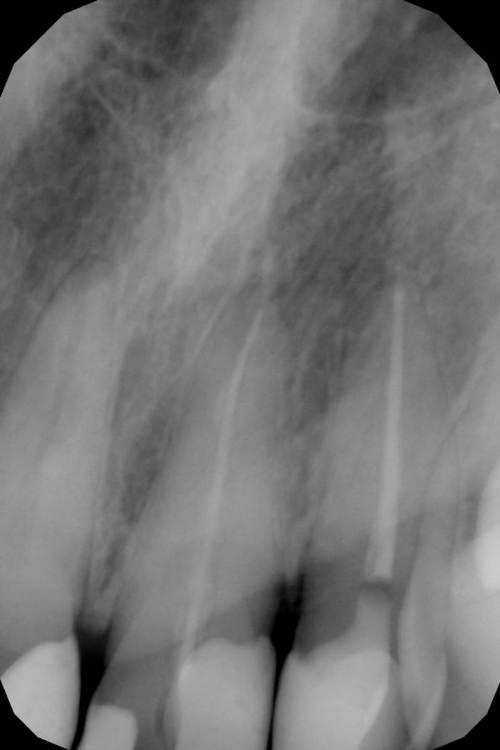

Patrick Опубликовано 14 апреля, 2021 Поделиться Опубликовано 14 апреля, 2021 Добрый день, скажите, пожалуйста, видно ли по этому снимку, что один из зубов нуждается в лечении? - Зуб реагирует на горячееи иногда ноет по ночам, но врач говорит, что нерв удален и болеть там нечему. Спасибо! Ссылка на комментарий

red_butler Опубликовано 14 апреля, 2021 Поделиться Опубликовано 14 апреля, 2021 на клыке нужно провести термометрию, а премоляры сделать Кт. и все зубы с этой стороны посмотреть 1 Ссылка на комментарий